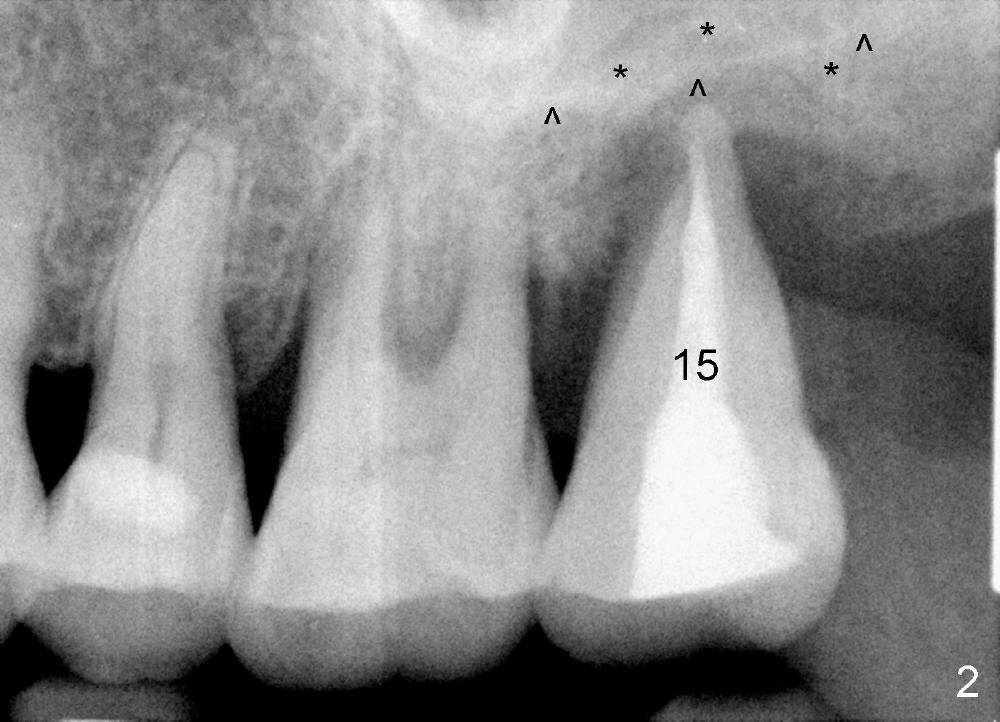

A 56-year-old female has recurrent infection and buccal gingival recession (Fig.1 *) after root canal therapy in the upper left 2nd molar (Fig.2). The extraction socket is single and large. Osteotomy forms by using a series of osteotomes (2-5 mm in diameter) mesiopalatal to the center of the socket. The sinus floor is thin (approximately 2-3 mm). The osteotomy is further enlarged by inserting 4.5-8 mm taps at the depth between 14 and 17 mm from the gingival margin. The last tap has barely achieved stability (Fig.3). It appears that the tap has almost obliterated the socket. Allograft is pushed into the sinus before placement of a 8x17 mm implant. The insertion torque is between 15 and 20 Ncm (Fig.4). The gingiva-level implant is slightly subgingival except buccal (Fig.5). To facilitate buccal gingival re-growth and cover the exposed implant surface, bone graft is placed subgingival (Fig.5 ^). The gingival sulcus is closed partially by placement of a thin strip of collagen membrane (not shown). The wound is protected by applying perio dressing.